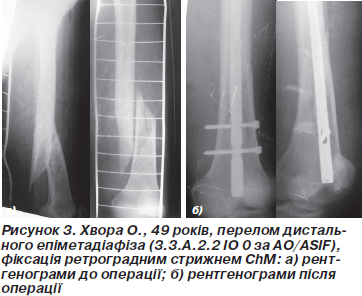

Техніка операції. Положення хворого на операційному столі на спині з зігнутими в колінних суглобах ногах. Ми використовували ретроградний доступ із медіальним парапателярним доступом із метою якомога меншого пошкодження власної зв’язки надколінка. Стрижень вводили через міжвиросткову заглибину точно посередині на 1 см наперед від передньої хрестоподібної зв’язки. Введення провідника та проведення по ньому стрижня виконували за стандартною методикою. Канал не розсвердлювали. Блокування стрижнів проводили під контролем спиці-провідника та ЕОП. Дистальну фіксацію проводили 2–4 блокуючими гвинтами (рис. 2, 3). При внутрішньосуглобових переломах кісткові фрагменти анатомічно репонували та виконували фіксацію болтом-стяжкою через отвори в стрижні, одночасно блокуючи стрижень. При дефектах стінки уламка використовувалась техніка poller-спиць.

При неможливості анатомічної репозиції суглобової поверхні вдавалися до відкритої репозиції, фіксацію виконували в режимі статичного блокування та за допомогою болтів-стяжок. Всього закрито проведено 17 (60,71 %) операцій, відкрито виконано 11 (39,28 %) операцій.